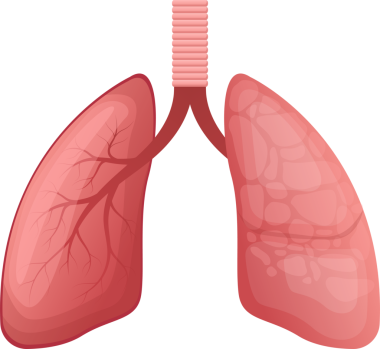

Sağlıklı Bir İnsan Akciğerinin Anatomisi, El Çizimi Suluboya Çizimi

Nefes alsuluboyaOksijenuçak yolculuğuHavalandırmaApexsolunumnefes borusubronşalveollersolunum yolukarbon dioksitSolunum SistemiAnatomik yapısıinsan akciğerMedikal illüstrasyonbronchiolesakciğer fonksiyonbasit örnekthoracic cavityrespiratory healthGaz değişimiVital kapasitehealthy lungmiddle lobetidal volumenormal lungüst lobalt lobbiyolojik diyagramBenzer İçerikler